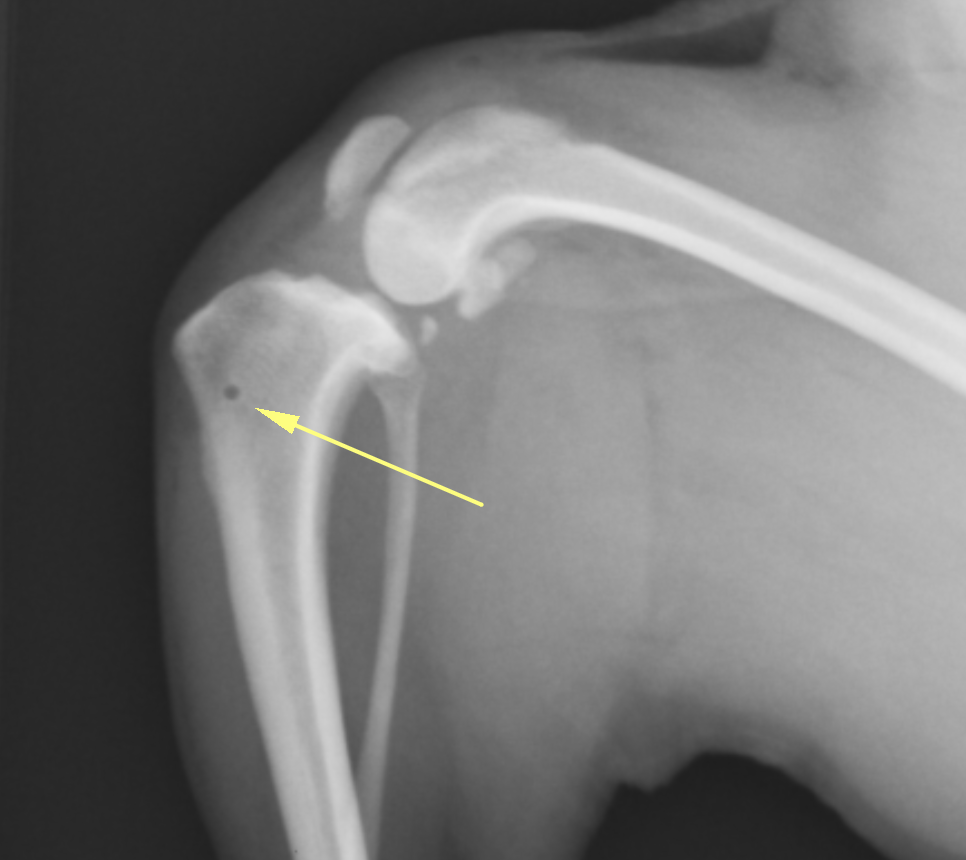

膝蓋骨滑落防止スクリュー:大腿骨にスクリューを打ち、4頭筋を制御することでパテラを落ちないようにする方法です。